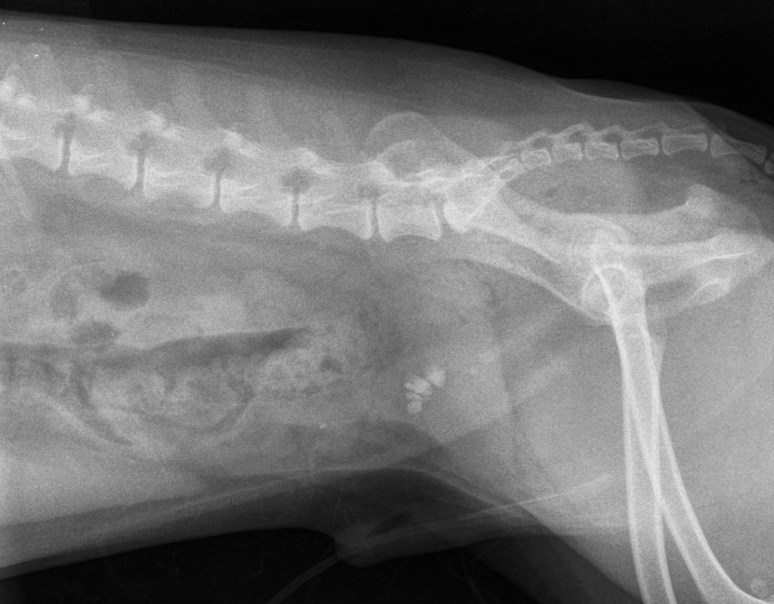

Voici deux images obtenues successivement, employant un système de cassettes et lecteur CR-30 de Agfa. Or, l’image du haut est de moins bonne qualité que celle du bas. Pourquoi selon vous ?